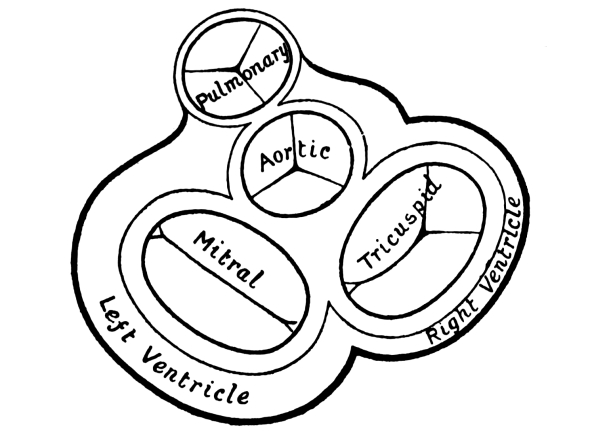

| 11. | Horizontal Section of the Heart, showing its Valves | 225 |